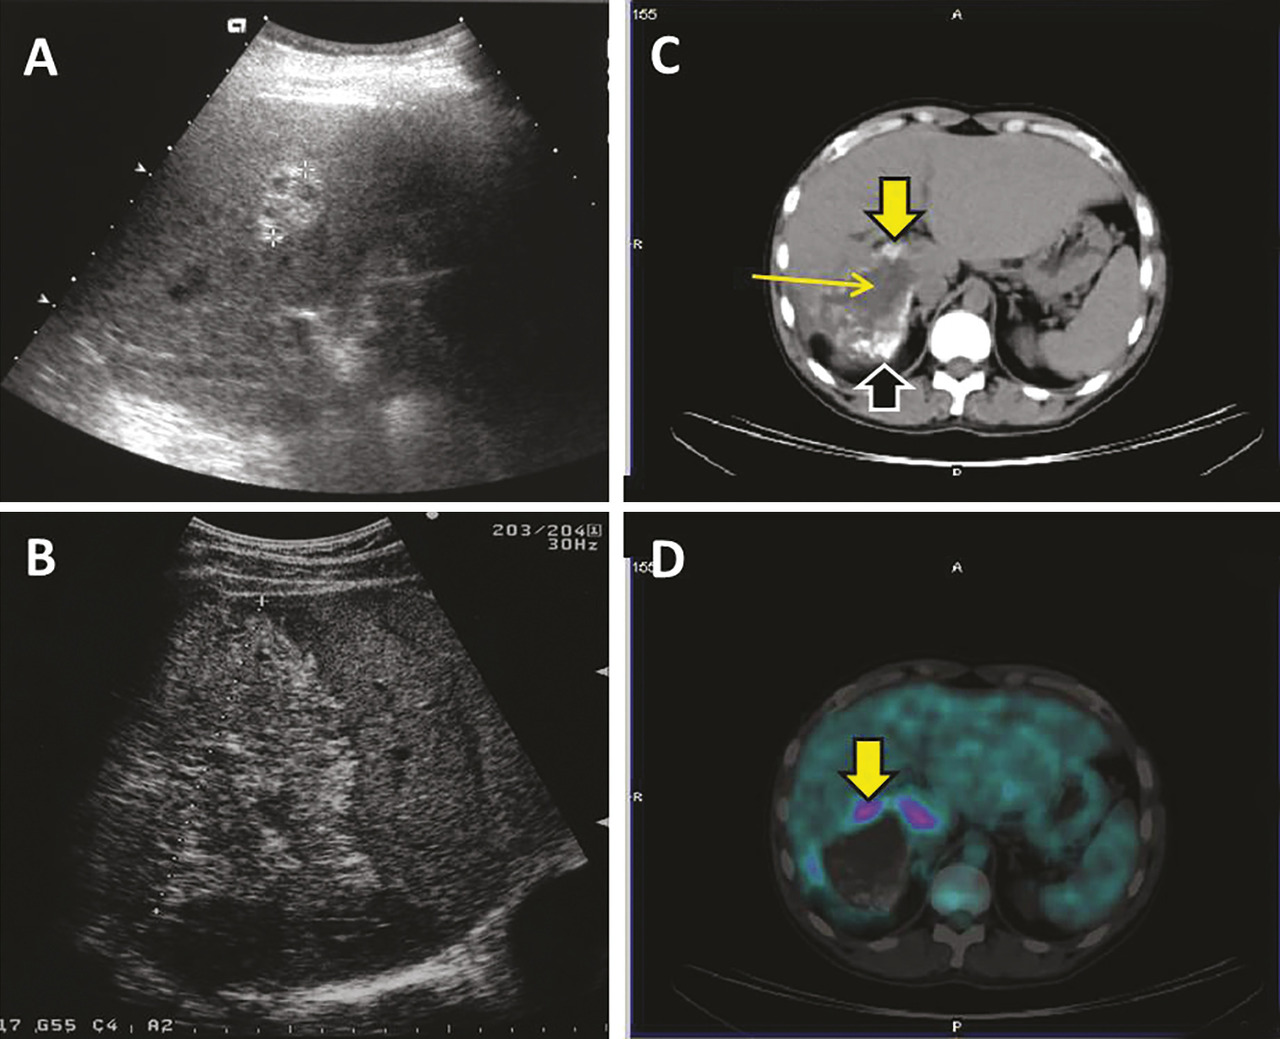

Échographie abdominale

L’aspect échographique habituel est celui d’un processus expansif intrahépatique pseudonéoplasique, d’échostructure hétérogène, à pré­dominance hyperéchogène, de contours irréguliers mal définis ;13 les zones de nécrose sont généra­lement de siège central et d’aspect trans-sonore pseudoliquidien (fig. 4). Les calcifications se présentent soit sous forme d’amas nodulaire, avec cône d’ombre acoustique postérieur net, soit sous la forme d’un semis de microcalcifications. Dans les formes débutantes, des aspects de diagnostic différentiel plus difficile sont observés : pseudo-angiomateux hyperéchogène, pseudo-métastatique, ou pseudo-abcès du foie. ­Couplée au Doppler pulsé et couleur, l’échographie peut indiquer une compression ou un envahissement des structures vasculaires portales, sus-hépatiques et cave inférieure.

La tomodensitométrie (TDM) permet de mieux apprécier le nombre, la taille et la topographie exacte de la ou des lésions.14, 15 Une classification morphologique qui décrit les différents types de lésions observés a récemment été proposée par un des centres de référence européen.16 C’est l’examen qui permet le mieux de mettre en évidence les calcifications dont la signification semble différente selon leur type : témoins de la dégénérescence du métacestode quand elles sont macronodulaires, mais associées à des paramètres évolutifs et de viabilité du métacestode quand elles sont micronodulaires, donnant un aspect poudré.17 Dans les formes évoluées, les lésions, le plus souvent uniques et touchant le foie droit, peuvent atteindre 10-15 cm de diamètre. Les lésions de diagnostic accidentel, en Europe, sont plus souvent que par le passé de petite taille (1-5 cm), et souvent multicentriques, suggérant que les lésions évoluées seraient dues à la confluence de plus petites lésions initiales (données du réseau XUUB). Contrairement aux tumeurs cancéreuses où le rehaussement ­périlésionnel est très net après ­injection de produit de contraste, les lésions d’échinococcose alvéolaire ne se rehaussent peu ou pas. La figure 4 illustre des aspects caractéristiques d’échinococcose alvéolaire en TDM. Un bilan d’extension pulmonaire et cérébrale par TDM doit être réalisé avant toute décision thérapeutique.18

TEP-TDM

Une hyperconsommation du fluoro- désoxyglucose (FDG) à la périphérie des lésions en tomographie par émission de positons couplée à la tomo­densitométrie (TEP-TDM), bien qu’en réalité associée à la réponse immunitaire de l’hôte, est considérée comme le meilleur signe d’activité métabolique du métacestode (fig. 4).3, 15, 20 Cependant, pour une évaluation optimale, il est indispensable d’ajouter une mesure 3 heures après l’injection du FDG aux mesures faites habituellement 1 heure après injection.21